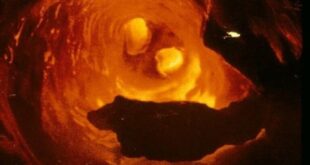

تصلب الشرايين .. أسبابه وأعراضه والوقاية منه يحدث تصلب الشرايين عندما يزداد سمك الأوعية الدموية التي تحمل الأكسجين والمغذيات من القلب إلى بقية الجسم، وزيادة هذا السمك يمكن أن يعوق تدفق الدم إلى أعضاء الجسم وأنسجته، وذلك لأن الشرايين السليمة مرنة بطبيعتها، ولكن مع مرور الوقت، يمكن لجدران الشرايين أن …

اسباب تصلب الشرايين .. وكيفية الوقاية منه وطرق علاجه لا شك أن معرفة أسباب المرض يساعدنا على الوقاية منه، لذلك نحن نذكر هنا اسباب تصلب الشرايين وكيف يمكن أن تحمي نفسك من هذا المرض عزيزي القارئ، وما هي سبل العلاج للمصابين بتصلب الشرايين، لذلك تابع معنا المقال التالي. تصلب الشرايين …